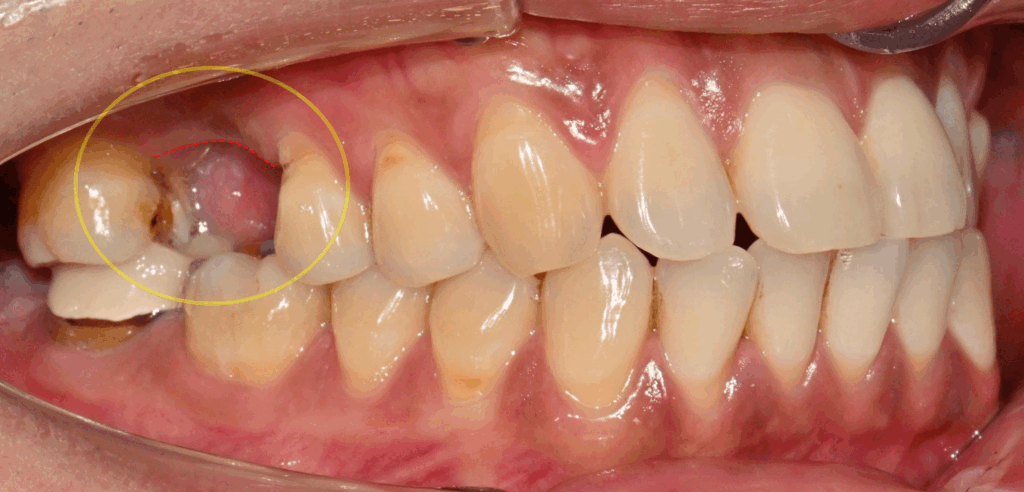

1. 충치의 의한 Cavitation

먼저 민락 치과 에서

사진에 표시한 곳을 보겠습니다.

[Cavitation]

즉 충치로 인해 치아 구조 자체에

‘공동’이 생긴 것을 뜻합니다.

처음 법랑질에서 머물던 병소가

점점 내부 구조로 파고드는 과정에서

치아 구조가 손상된 겁니다.

해당 치아 구조의 손상은 크지만,

적절한 치료만 진행된다면

충분히 개선할 가능성이 큽니다.

다만 손상 부위가 크기 때문에

내부는 레진으로 채워 넣는 방식으로

치관을 보강하고 경과를 지켜봅니다.